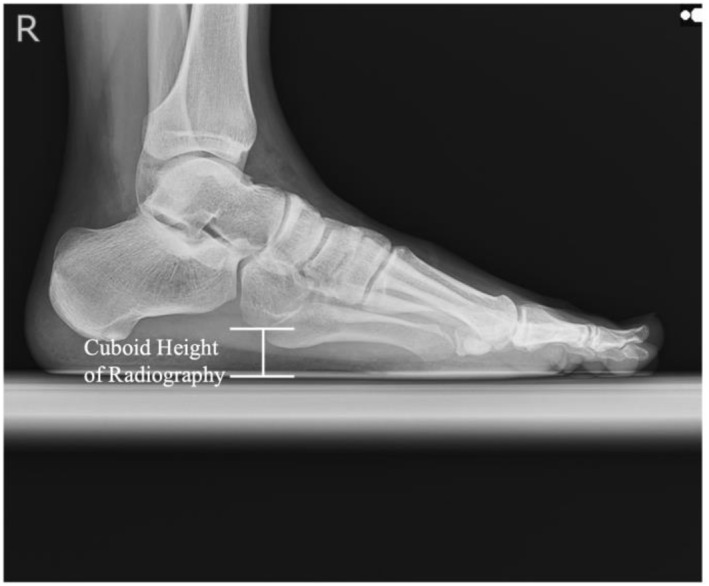

Introduction: The lateral longitudinal arch (LLA) is an essential structure of the foot. However, LLA evaluation methods remain underexplored compared to those of the medial longitudinal arch (MLA). This study sought to develop a method for measuring the cuboid height, the keystone of the LLA, using ultrasonography and to verify its correlation with radiography, as well as intrarater and interrater reliability.

Methods: This cross-sectional study included 21 university students (14 males and seven females). The cuboid height was measured using radiography and ultrasonography. The validity of ultrasonographic measurements was assessed through correlation with radiographic measurements and Bland-Altman analysis. Intrarater and interrater reliabilities were evaluated using intraclass correlation coefficients (ICCs).

Results: A strong correlation was observed between cuboid heights measured using radiography and ultrasonography (r = 0.98, p < 0.01). The Bland-Altman analysis revealed a fixed bias of -0.71 mm (95% confidence interval [95% CI]: -0.96 to -0.46 mm). Intrarater and interrater reliability for ultrasonographic measurements were almost perfect, with ICCs of 0.98 and 0.99, respectively.

Conclusions: Cuboid height measurements using ultrasonography demonstrated high validity and reliability. This method offers a noninvasive and cost-effective alternative to radiography, with potential clinical applications in the evaluation of LLA and related conditions such as cuboid syndrome and lateral foot injuries.